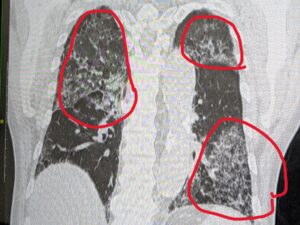

70代の男性の方です。

10日前から息が苦しくて、奥様と受診されました。

CTで間質性肺炎がわかりました。